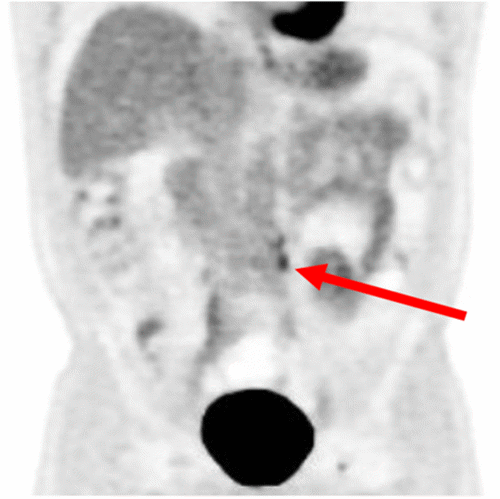

Approximately two years after his initial surgery, a rising carcinoembryonic antigen (CEA) level prompted investigation. A computed tomography (CT) scan identified a 2.5 cm left para-aortic lesion at the IMA origin, which biopsy confirmed as metastatic adenocarcinoma. This first recurrence was treated with stereotactic body radiation therapy (SBRT) to a total dose of 40 Gy in 5 fractions, after which his CEA levels and imaging findings normalized. Two years following SBRT, his CEA levels again began to rise, and surveillance CT imaging demonstrated regrowth of the tumor in the previously irradiated left para-aortic area. He received systemic chemotherapy for three months with a good clinical response. However, after a subsequent chemotherapy holiday, his CEA rose once more. Repeat CT and positron emission tomography (PET) scans (Figure 1) confirmed an isolated recurrence in the same left para-aortic location. After multidisciplinary tumor board discussion, which included input from a new surgical oncologist, the decision was made to pursue surgical resection.

Figure 1. Preoperative Imaging of Para-aortic Rectal Cancer Recurrence. Published with Permission

Composite image demonstrating the recurrent para-aortic metastasis. (A) Coronal contrast-enhanced CT scan revealing a soft tissue mass (arrow) in the left para-aortic region, consistent with nodal recurrence. (B) Corresponding PET scan image showing intense fluorodeoxyglucose (FDG) uptake (arrowhead) within the left para-aortic lesion, indicative of metabolically active malignant disease